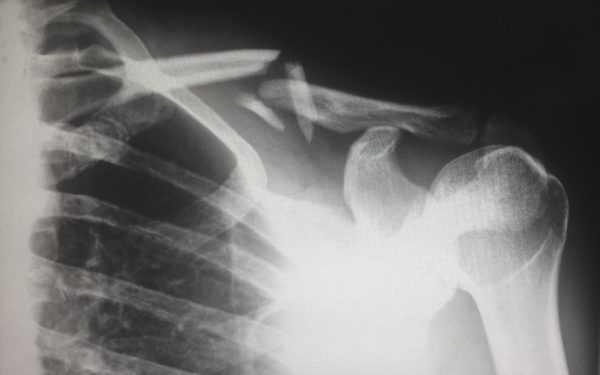

近年の医療現場ではさまざまな場面でAIが活躍するようになってきています。

そして、放射線業界はAIとの親和性が高い領域と言われています。

CTやMRIなどの最新の医療技術を駆使して診断を行っていく分野だけに、将来的には臨床現場へのAI導入に際して、有用性と妥当性を判断する役割が期待されているのです。

また、放射線科は検査と治療の両方に関わる特殊な診療科です。

特にがん治療などでは放射線治療の認知度も向上しており、予防分野のみならず治療の1つとして放射線科への需要はこれからますます高まっていくと見込まれています。